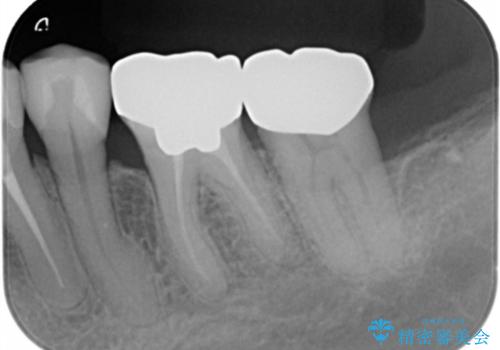

銀歯を除去したのち、虫歯を丁寧に除去し、歯を残せるのかどうかをしっかりと評価し、長期的な予後を見据えた虫歯治療を行っていきます。

銀歯の下で虫歯が再発していた歯は、無理に残しても割れてしまう可能性が非常に高いと考えたため、相談の上抜去を行いインプラント治療を行っていくこととしました。